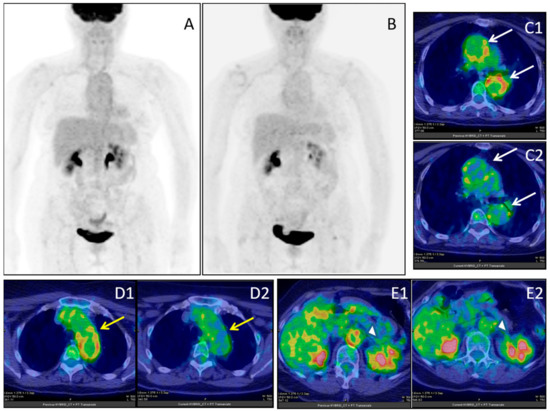

- Markovic SNGalli, F.; Suman, V.J.; Nevala, W.K.; Paulsen, A.M.; Hung, J.C.; Gansen, D.N.; Erickson, L.A.; Marchetti, P.; Wiseman, G.A.; Signore, A. Non-invasive visualization of tumor infiltrating lymphocytes in patients with metastatic melanoma undergoing immune checkpoint inhibitor therapy: A pilot study. Oncotarget 2018, 9, 30268–30278. [Google Scholar] [CrossRef]

- Kong, B.Y.; Menzies, A.M.; Saunders, C.A.; Liniker, E.; Ramanujam, S.; Guminski, A.; Kefford, R.F.; Long, G.V.; Carlino, M.S. Residual FDG-PET metabolic activity in metastatic melanoma patients with prolonged response to anti-PD-1 therapy. Pigment Cell Melanoma Res. 2016, 29, 572–577. [Google Scholar] [CrossRef]